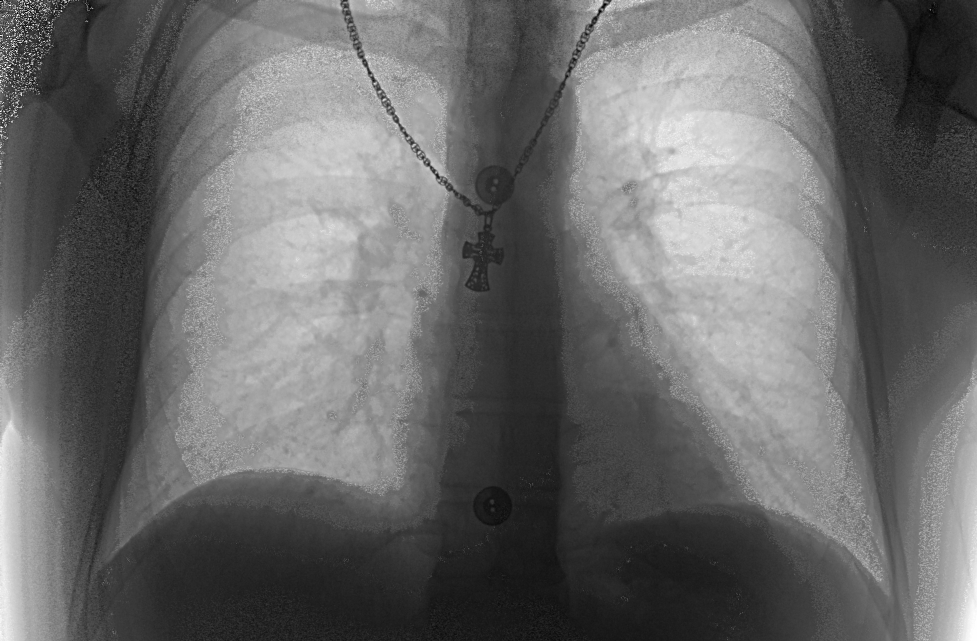

Дело было так: в одие совсем не прекрасный день случился пожар в пультовой. Загорелся потолочный светильник, упал на диван и т.д. Все погасили. Потери - бесперебойник, монитор. Все в копоти. К счастью АРМ и пульт выжили. После косметического ремонта произвели чистку питающего и стойки от копоти, которой было очень много. Запустили - вроде работает. Через день звонок - не идут боковые проекции. Снимки аналогичные вложенным. Еще через полдня на плате сетевого фильтра произошло КЗ - очень хорошее КЗ ireful все 3 фазы,земля и нолик. Плату починили, пришлось менять плату управления.Теперь и прямые снимки тоже такие же. Снимки сделаны без экспонометра, ибо экспонометр глючит - отключается слишком рано и снимки все в "снеге", т.е. не пробитые. Может у кого появятся идеи?

100_12.bmp (1.79 Mb) · 100_25.bmp (1.79 Mb)

По поводу тестера - согласен. Но легкие? Режимы выставлены по рекомендациям электроновцев.Снимки до пожара - режимы аналогичные 100 кВ прямые около 10 мАс, боковые около 16 мАс. Рекомендовали откалибротваь трубку - не помогло. При калибровке камеры в tunerxp, например при калибровке фона когда работает одна камера без высокого картинка получается будто бы присыпанная манной крупой. Множество точек на черном фоне. Как должно быть пока не ясно. Поищу другой аппарат и посмотрю какой фон должен при калибровке камеры.

Вот вам господа окончание грустной истории - вызвали инженера с завода. Приехал, провозился субботу с воскресеньем и вынес вердикт - проще поменять аппарат, чем этот ремонтировать. Генератор полностью от копоти можно вычистить только в заводских условиях, вылетел АЦП толи на плате граббера, то ли на плате камеры - от того и снимки такие, т.к. при этом уменьшается число градаций серого. Надо менять кабель "Камера-граббер", а может и матрица накрылась и т.д.